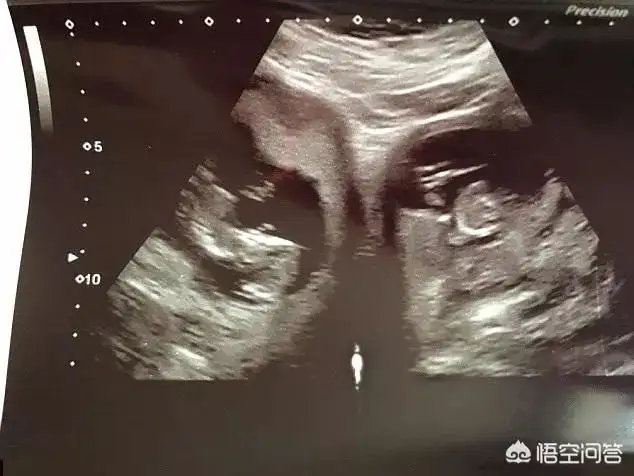

到了2月份,医生在进一步的检查中发现,詹妮弗居然是双子宫,一对双胞胎个占据其中的一个宫腔。

詹妮弗这种状况,并不是有两个独立的子宫,而是一个子宫体,中间被一个隔膜不完全分为两个宫腔,这在医学上被称为双角子宫(bicornuate uterus)。